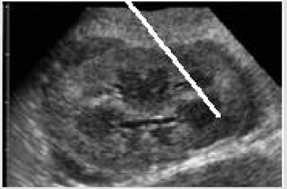

Describe M-mode for heart U/S.

A

Represents movement of structures over time.

Initially a B-mode image is acquired and a single scan line is placed along the area of interest.

M-mode shows how the structures intersected by the line move toward or away from the probe over time.

One dimensional image of structures.

Only structures associated with the cursor are seen. Depth on the Y axis, time on the X axis.

Records subtle change in wall and valve motion (chamber dimensions, fractional shortening, ejection fraction).

Used for accurate measurement of size.

M-mode in cardiac U/S